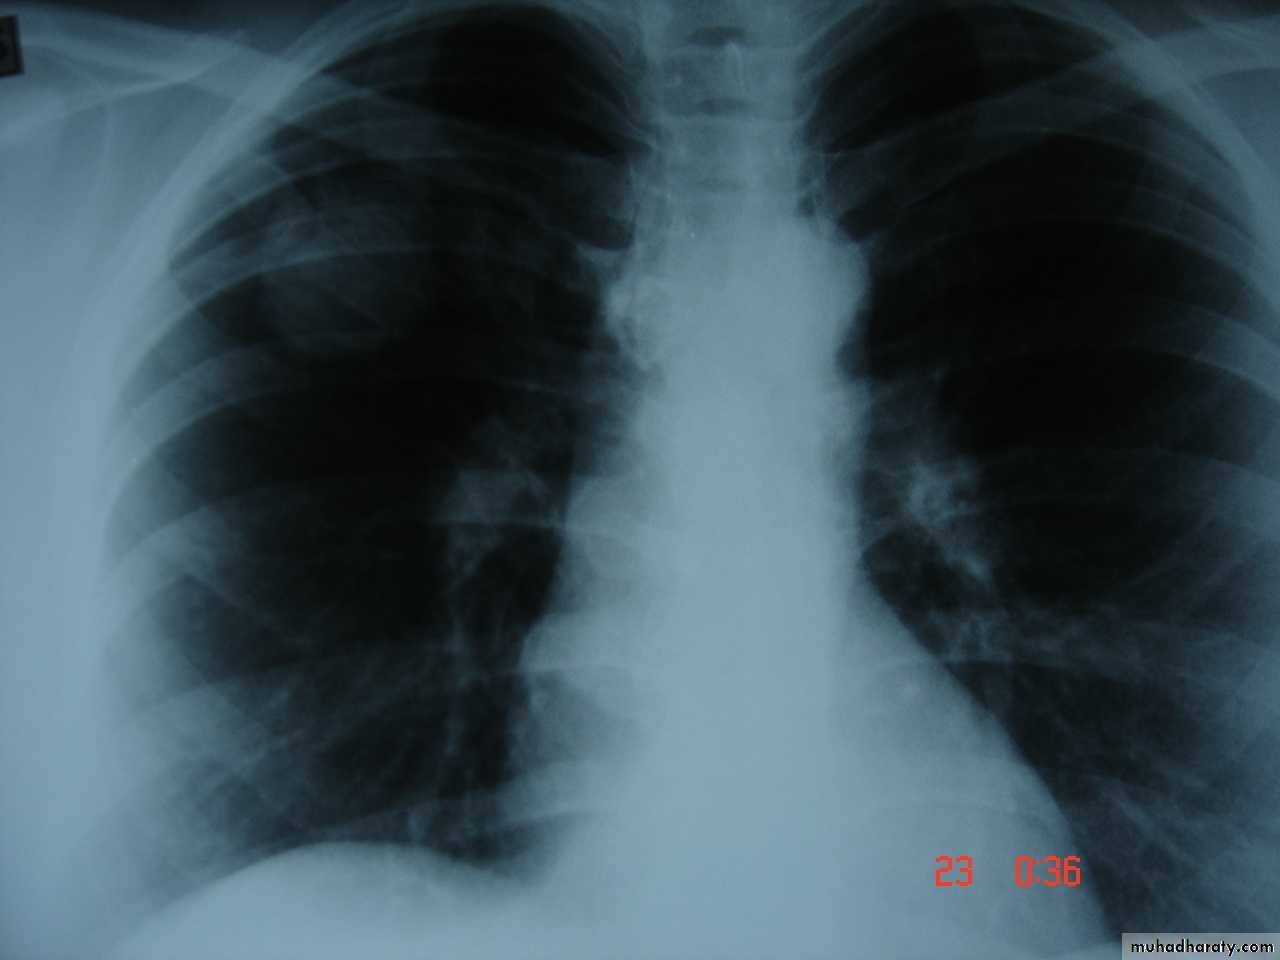

• Pathology :-A-Central type is the commonest (75%).It arises in one of the main bronchi or their primary division leading to bronchial obstruction with secondary changes in the lung such as atelectasis .B-Peripheral type (25%) arises from the smaller bronchi and remains symptom less for long time .

Histologically Squamous cell Ca (SCC) 60% , smoker , centrally located ,metastasizes to mediastinal & supraclavicular LN . Adenocarcinoma (15% ) , located peripherally , more in women .Tends to metastasizes to the liver , brain ,bone & adrenals in addition to the LN Undifferentiated carcinoma (oat) cell carcinoma and large cell carcino(20-30%) which includes small ma Alveolar cell carcinoma , located peripherally ,metastasizes to the liver and adrenalsRecent classification..Non small & small cell carcinoma

• Clinical features :-1- cough dry or productive2-Haemoptysis3-Chest pain4-Dyspnea5-Pleural effusion6-Anorexia & loss of weight7-Clubbing of the fingers8-Hoarseness of the voice (recurrent LN)9-Dysphagia involvement of the esophagus10-Hormonal syndromes ..ectopic ACTH , ADH, hypercalcaemia ,carcinoid syndrome

• Diagnosis

• Clinical , sputum cytology

• Chest X-ray ,CT chest ..